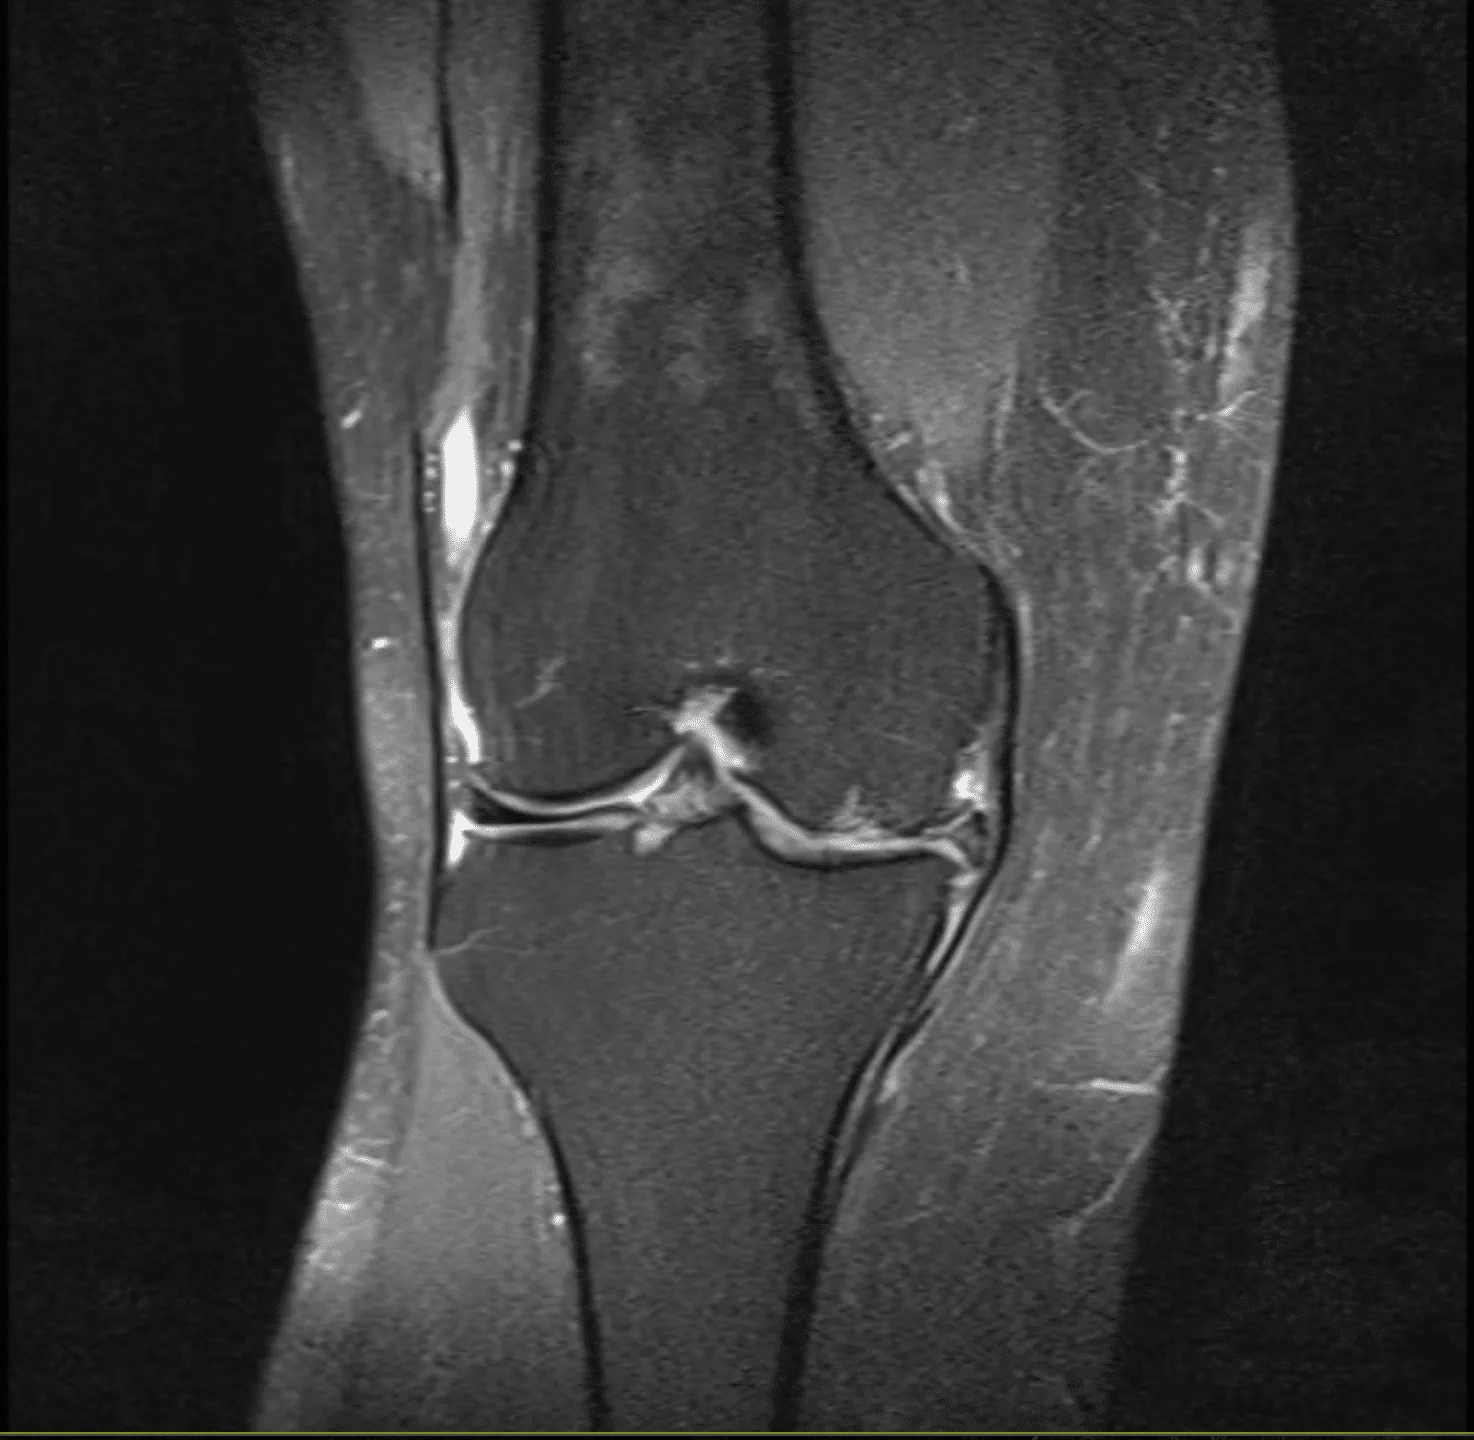

Meniskusverletzung / Meniskusschaden

Der Meniskus ist ein ringförmiger Stoßdämpfer im Gelenk. Ihr Knie besitzt gleich zwei davon: Den Innen- und Außenmeniskus. Verletzungen des Meniskus können akut bei einem (Sport-) Unfall auftreten, häufige jedoch im Rahmen eines Verschleißes über einen längeren Zeitraum entstehen. Eine Meniskusverletzung geht mit einer verminderten Funktion als Stoßdämpfer einher, im schlimmsten Falle kommt es zu einem kompletten Funktionsverlust. Es droht dann ein verstärkter Verschleiß (Arthrose).

Initial ist häufig ein konservativer Therapieversuch möglich. Ab einem gewissen Ausmaß ist jedoch die arthroskopische Operation mit (Teil-)Entfernung des Meniskus oder Meniskusnaht indiziert.